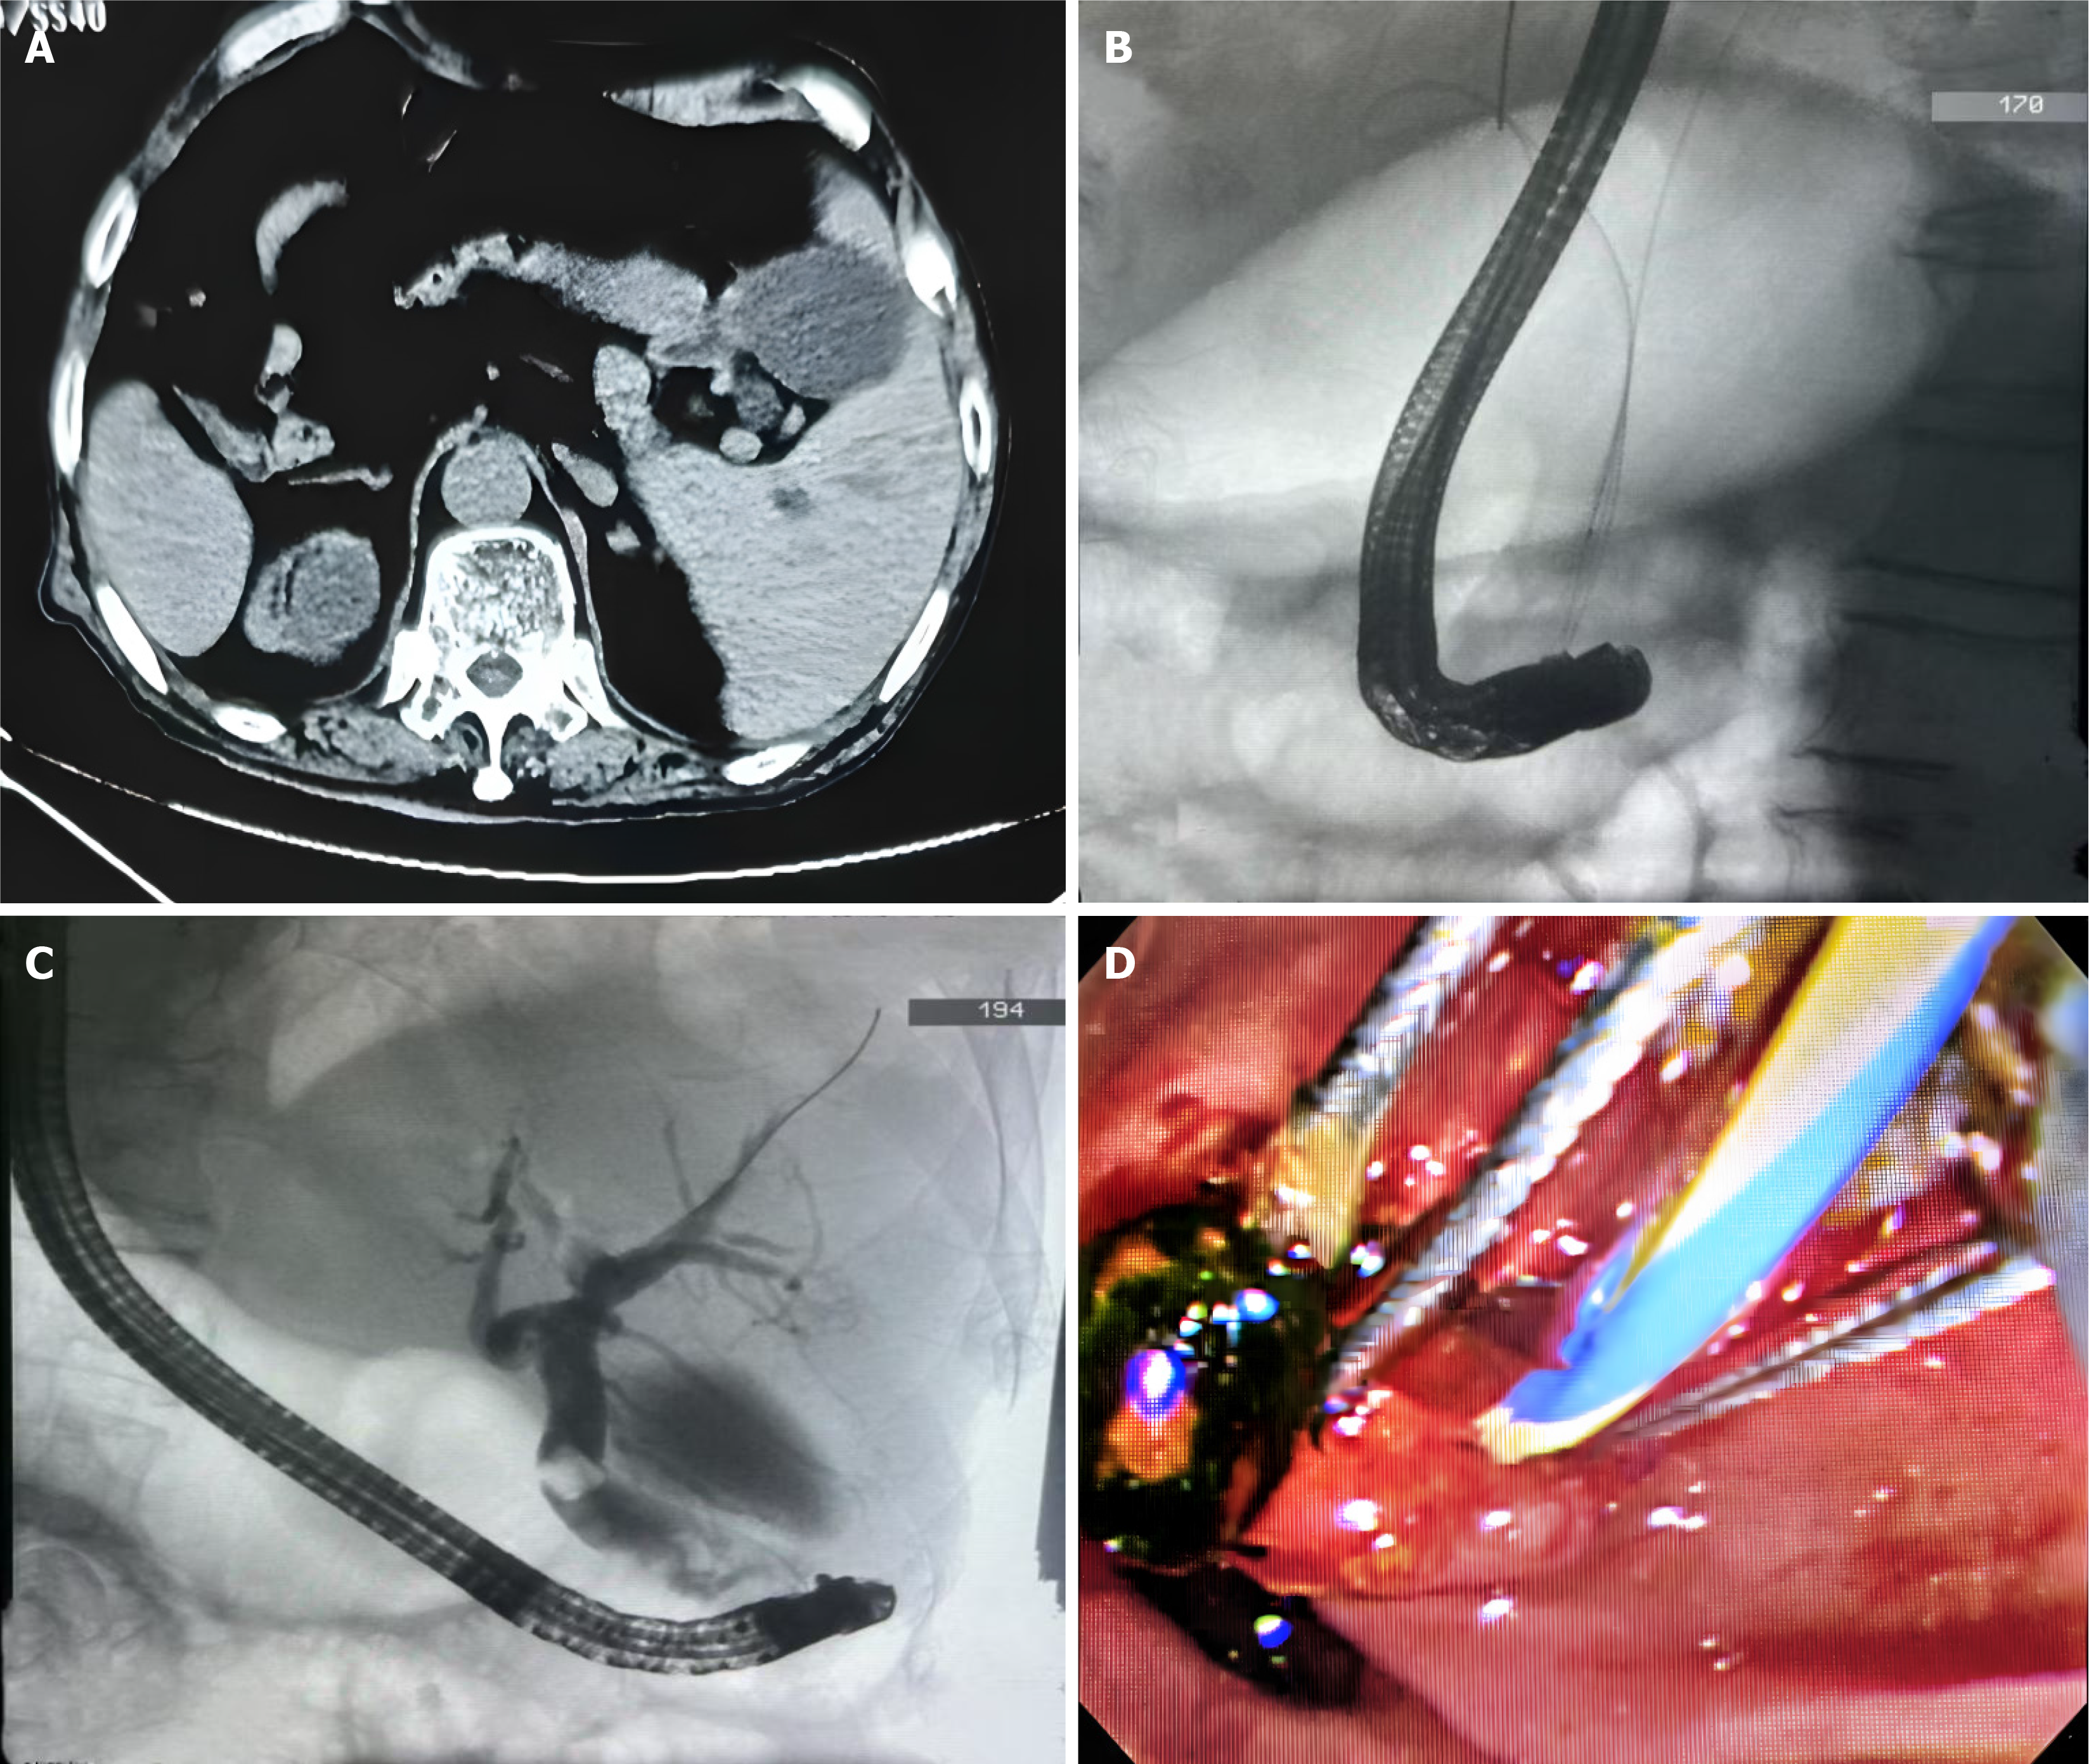

A chest X-ray, electrocardiogram, and echocardiogram confirmed the previous diagnosis of dextrocardia. Computed tomography scans revealed that the liver was primarily located on the left side of the abdomen, while the spleen was on the right. The gallbladder was found on the left side, marginally enlarged, with visibly dilated bile ducts. Mild dilation of the intrahepatic bile ducts and a dense shadow at the terminal end of the common bile duct was observed (Figure 1A).

Thereafter, endoscopist used sphincterotomes to carry the guidewire and re-attempt bile duct cannulation. While inserting the catheter with sphincterotomes, which provided axial traction on the pancreatic duct wire. This facilitated separation of the bile and pancreatic ducts, allowing successful bile duct cannulation (Figure 1B). Iohexol contrast revealed an expanded common bile duct with a stone shadow (Figure 1C). A small incision was made in Oddi’s sphincter, and a ball and single-use balloon dilatation catheters were used to dilate the papilla and the lower bile duct segment. Purulent bile flowed out, and a stone basket and single-use stone retrieval balloon were used to remove a yellow-green hard stone into the intestinal lumen (Figure 1D). The bile duct was cleared with a single-use stone retrieval balloon. A subsequent contrast confirmed that the common bile duct was patent.